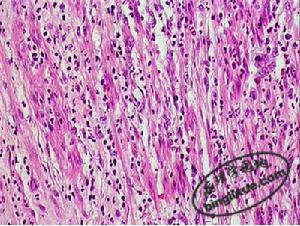

(一)非特異性慢性炎非特異性慢性炎,病變主要表現為纖維母細胞、血管內皮細胞和組織細胞增生,伴有淋巴細胞、漿細胞和巨噬細胞等慢性炎細胞浸潤,同時局部的被覆上皮、腺上皮和實質細胞也可增生。慢性炎症還可伴有肉芽組織的形成,這類炎症常見於有較大的組織缺損,此時肉芽組織在慢性膿腫、瘺管和慢性黏膜潰瘍的吸收和分解上起著重要作用。

炎性息肉(inflammatory polyp) 是在致炎因子長期作用下,局部黏膜上皮和腺體及肉芽組織增生而形成的突出於黏膜表面的肉芽腫塊。常見於鼻黏膜和宮頸。炎性息肉大小不等,從數毫米至數厘米,基底部常有蒂,鏡下可見黏膜上皮、腺體和肉芽組織明顯增生,並有數量不等的淋巴細胞和漿細胞浸潤(圖2)。

圖2結腸息肉炎性假瘤(inflammatory pseudotumor) 是指炎性增生時形成境界清楚的瘤樣腫塊,常發生於眼眶和肺。組織學上炎性假瘤由肉芽組織、炎細胞、增生的實質細胞及纖維組織構成。X線檢查時,其外形與腫瘤結節相似,因而被稱之為炎性假瘤,應注意與真性腫瘤鑑別。特別是肺的炎性假瘤在組織結構上較為複雜,有肉芽組織增生、肺泡上皮增生(但無異型性)、肺泡內出血、含鐵血黃素沉積、巨噬細胞反應等,並可有吞噬脂質的泡沫細胞和多核巨細胞。此外,還有淋巴細胞和漿細胞浸潤。